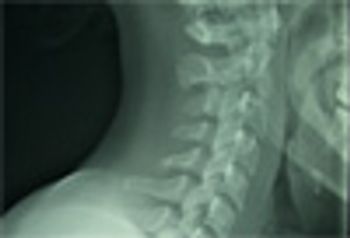

A woman in her 20’s presents for care after 9 days of sore throat and subjective fevers followed by neck stiffness that developed over the last 2 to 3 days. The pain is exacerbated by swallowing and any neck motion. She has had sore throats before, but never this bad or this long and never that made her neck stiff.